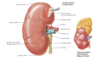

venous drainage of kidney

R & L renal V

- anterior to A

- L receives L suprarenal and L gonadal

drain to IVC

L passes anterior to aorta, posterior to desc SMA

Peri-nephric abscess

spread to pelvis due to fascial attachment

- DOES NOT SPREAD TO ADJ KIDNEY

causes:

- UTI

- staph aureus

- DM

- lsions of urinary tract: stones, cyst